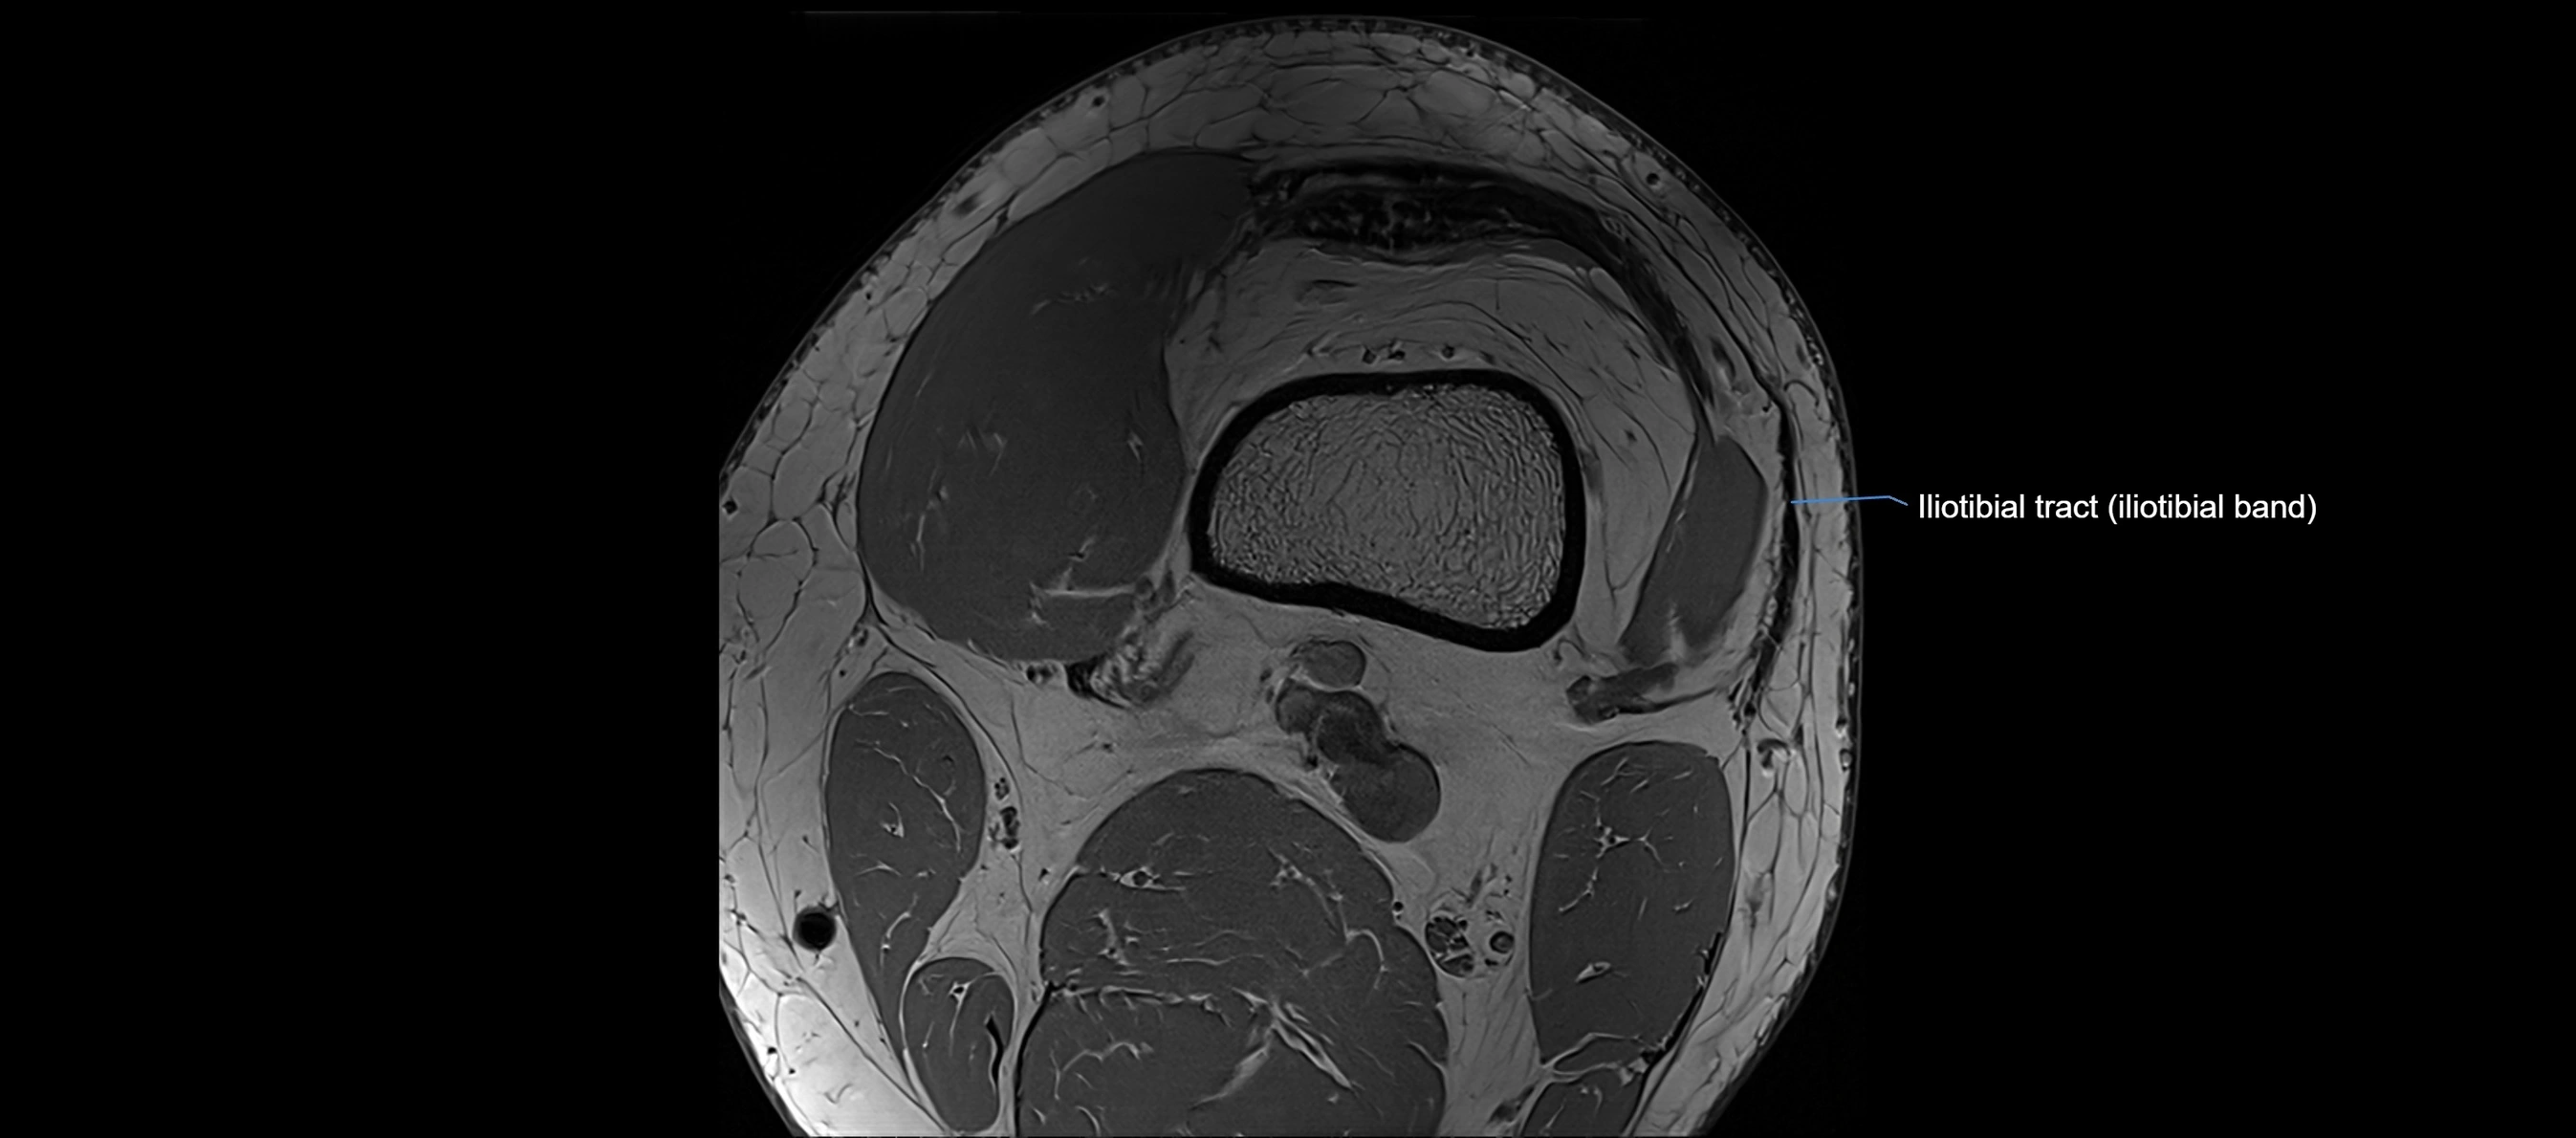

MRI images

image